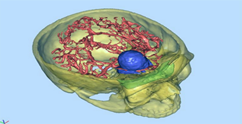

1) MARCO ESTEREOTAXIA: Marcación estereotáctica para lesiones profundas , craneotomias guiada por estereotaxia y/o asistidas por Neuronavegación. (Incluirá el equipo)

VI. CIRUGIA FUNCIONAL , ESTEREOTAXIA Y EPILEPSIA

Se prestará la asistencia para la alternativa terapéutica en casos de enfermedades refractarias a tto médico, cirugía en casos de movimientos

anormales (parkinson) , temblor esencial mediante la implantación de estimuladores.